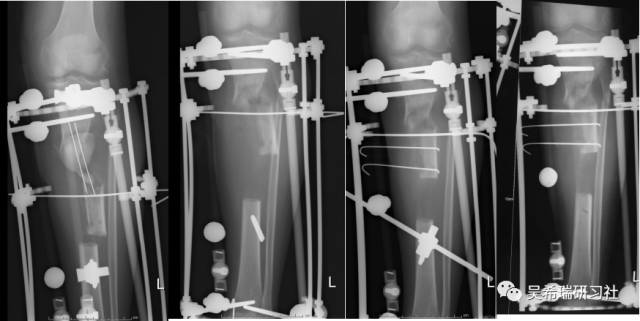

小腿骨折继发感染骨髓炎反复皮瓣9个月未下地骨质疏松继发肥胖

TIPS:9个月反复皮瓣未下地骨质严重疏松病灶清除后应用表面羟基磷灰石涂层骨圆钉半开放植骨 + 骨搬移骨水泥设计为自行吐出伤口开放换药走路骨质改善、骨愈合治疗足下垂